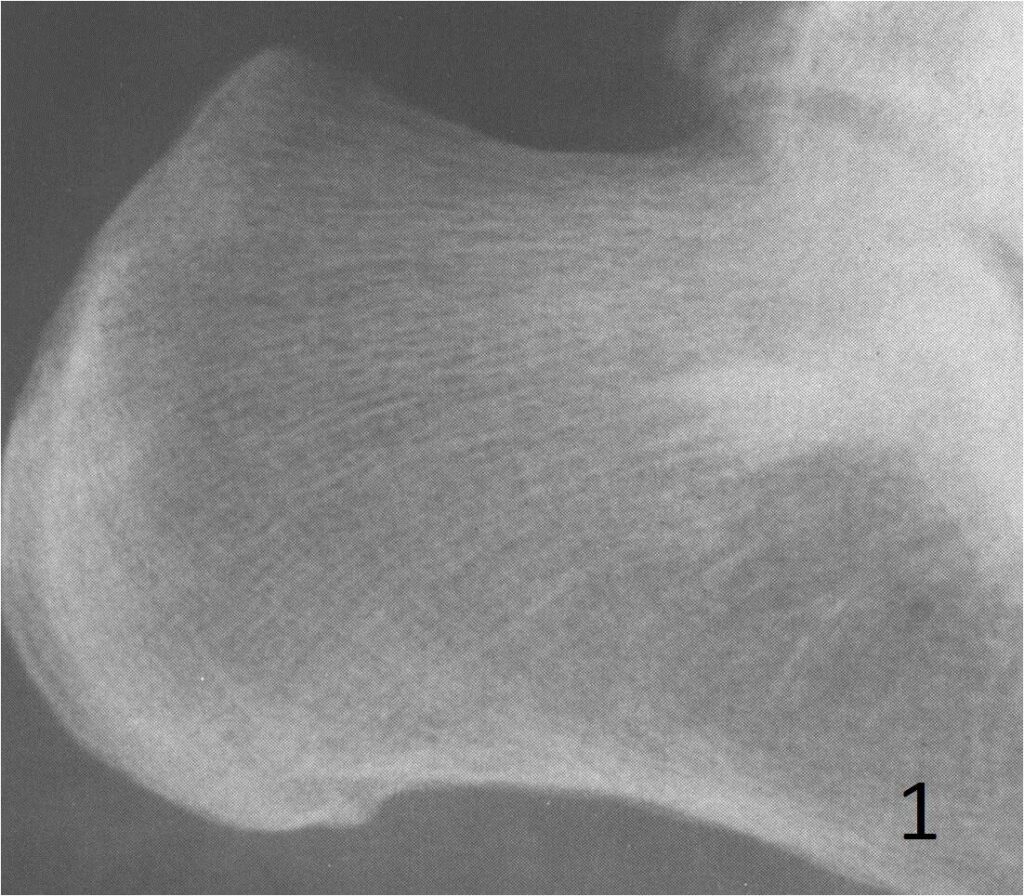

On radiographs, enostoses are round to oval and sclerotic lesions, without a periosteal reaction or bony destruction (Fig. 1). They have in the periphery of the lesion “feather-like spicules”, resembling a “brush border” making this feature useful to recognize them. The spicules at the periphery blend in with the surrounding bony trabeculae. CT shows a blastic lesion, without periosteal reaction with radiating spicules at the periphery. The spicules may be more discernible on a CT scan than on plain x-ray (Fig. 2). MRI, shows no bone disruption or bony destruction, and is hypointense on both T1 and T2 weighted MR images. Bone islands are inert on bone scans, except when they are large. They may be quite active and hence may be worrisome for a malignancy.